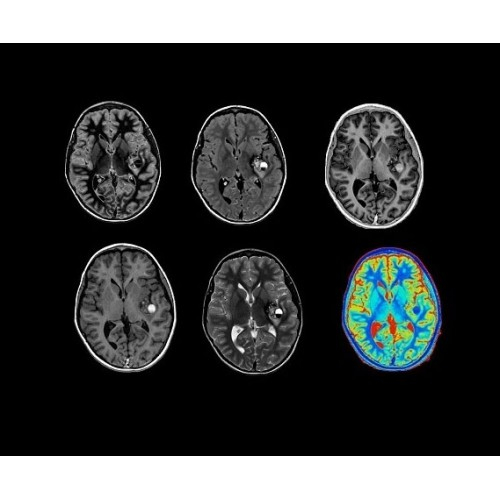

• Q.Clear — в основу технологии легли накопленные знания о том, как минимизировать помехи при реконструкции и получить четкое изображение. При значительном улучшении качества изображения сохраняется точность расчетов. Сочетание технологии TOF и реконструкции Q.Clear — ваш надежный помощник для получения точных и достоверных данных.

Новейшая платформа SIGNA Works4 повышает производительность ключевых технологий визуализации GE Healthcare. SIGNA Architect поставляется с предустановленными стандартными приложениями. Расширенные функции SIGNA Works с возможностью обновления позволят устанавливать новые приложения в соответствии с растущими потребностями вашей клинической практики.

Стандартный пакет приложений SIGNA Works позволит вам достичь желаемых результатов в клинической практике благодаря набору высокоэффективных средств визуализации. Программные приложения, входящие в состав данных клинических пакетов, включают широкий спектр контрастов, функции обработки 2D- и 3D-данных, а также возможность коррекции артефактов движения. SIGNA Works предоставляет набор инструментов, необходимых для проведения эффективного клинического исследования.

• Специальный пакет приложений для измерения и сравнения объемных изображений ЦНС с нормами поможет вам в диагностике нейродегенеративных заболеваний, а дополнительные инструменты визуализации — в постановке точного диагноза с помощью бета-амилоидов и радиоизотопных маркеров ФДГ.